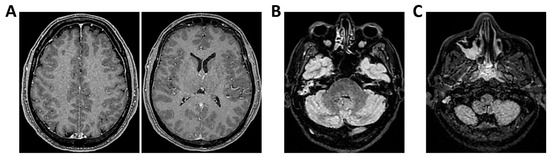

Figure 1.

MRI of patient 1 group 1. A 74-year-old woman with a history of atrial fibrillation, ischemic heart disease, anxiety-depressive syndrome, and hypertension was found at home in a stuporous state. She had experienced asthenia and fever in the preceding days and had initiated ciprofloxacin treatment. On arrival, laboratory exams showed leukocytosis (11,930/mm3, 90.4% neutrophils), elevated INR (1.92), and markedly increased inflammatory markers. Arterial blood gas revealed hypoxemia (pO2 55 mmHg), requiring mechanical ventilation with 35% FiO2. Brain CT was unremarkable, showing no acute lesions or signs of raised intracranial pressure. Chest CT revealed bilateral posterior-basal consolidations with air bronchograms (more severe on the left), a smaller consolidation in the left upper lobe, and bilateral pleural effusions, consistent with bronchopneumonia. A lumbar puncture was initially contraindicated due to coagulopathy. Due to worsening neurological status (GCS 6), the patient was transferred to the ICU, intubated, and underwent lumbar puncture. On day 2, TCCD showed PI values of 0.62 (right) and 0.71 (left), with no signs suggestive of intracranial hypertension. (A) 3D axial FLAIR sequence shows multiple bilateral hyperintense areas, without mass effect. (B) Some of these present diffusion restriction in axial DWI sequence with the largest located in the left middle and superior frontal gyrus. There is also a subtle pachymeningeal enhancement in the bilateral fronto-temporal region. Supratentorial and infratentorial ventricular system is normal in size and configuration, with no midline shift or hydrocephalus.

Regarding etiology, two cases, case 1 and 5 (40%), were due to pneumococcal meningitis, while the remaining were neurotoxoplasmosis (n = 1, 20%) (case 2), Varicella-Zoster virus meningoencephalitis (n = 1, 20%) (case 3), and meningoencephalitis of undetermined origin (n = 1, 20%) (case 4). Three out of five patients demonstrated normal or mildly elevated pulsatility indices (PI ≤ 1.18) and no waveform signs of intracranial hypertension. In these cases, MRI findings were either normal or showed non-specific alterations, such as mild pachymeningeal enhancement or limited subcortical lesions, without mass effect or restricted diffusion. All three patients in this subgroup experienced full neurological recovery at 28 days (GOS 5) (Table 2 and Figure 1, Figure 2 and Figure 3).

In contrast, two patients in the same group presented with elevated PIs. One patient with HIV and neurotoxoplasmosis exhibited bilateral flow abnormalities (PI 1.96 on the right; 1.25 on the left), with multiple supratentorial ring-enhancing lesions on MRI, suggestive of cerebral toxoplasmosis. The patient showed no significant clinical improvement at 28 days (Table 2 and Figure 4).

Another patient with Varicella-Zoster meningoencephalitis had a critically elevated left-sided PI (3.6) and MRI findings limited to hippocampal hyperintensity (Table 2 and Figure 5).

Despite subtle structural abnormalities, the patient died within 28 days of admission. In both cases, high PI values accompanied poor neurological outcomes, highlighting the prognostic role of TCCD in identifying impaired cerebrovascular reserve and autoregulation failure.